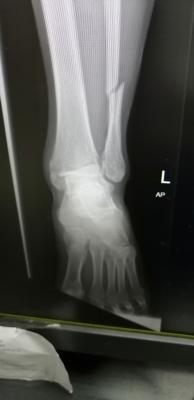

Mai scare me leg. My scan results are out. Ligament tendon all good. Just bone broken and one part dislocated. Broken part all screws. Dislocated, screwed back to strengthen.

just wait untill fractured heal...for time being slowly get range movement ankle and partially weight bearing if more than 6 week..and ostechondral injury cannot be seen in xray or ct scan..even sometimes mri also can be miss..u definitely have it as your medial malleolus fractured involving ankle joint which have cartilage over there..Mai scare me leg. My scan results are out. Ligament tendon all good. Just bone broken and one part dislocated. Broken part all screws. Dislocated, screwed back to strengthen.